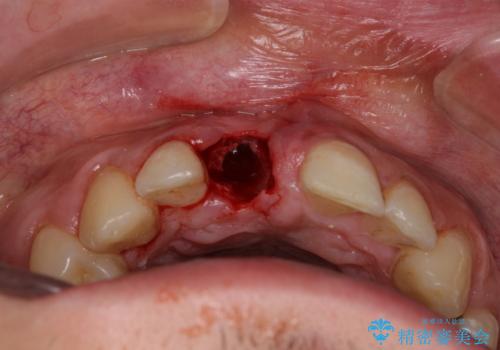

磨き残しなどによるプラークの付着が多いため、仮歯の用意と手術アポイントの調整を行っている間に口腔内のクリーニングなどを施し、環境がある程度改善されたのちに、抜歯即時インプラント埋入、即時荷重(インプラント埋入時に仮歯の装着)の予定で治療を行うこととしました。

度重なる脱離により、表側の炎症が非常に強くなっており、歯を支える骨が失われている状態でした。

そのため、現在の位置よりも歯と歯肉の位置が退縮する方向に移動する可能性があり、前歯2本の歯肉位置が大きくずれることとなるため、本人との相談のうえ、天然歯が萌えているような歯肉状態とはならないものの、2本の段差が少ない状態にて治療を終えることとなりました。